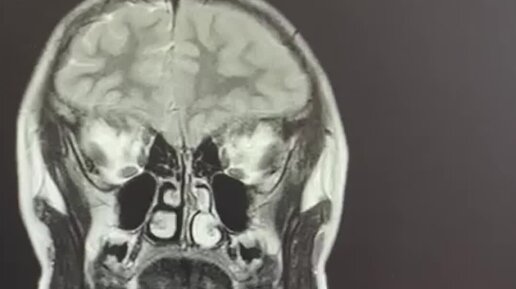

Клинический случай: личинки эхинококка в головном мозге подростка